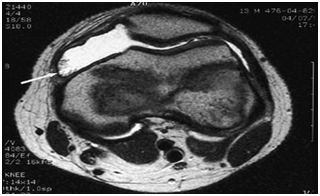

The classic plain radiographic findings of PVNS consist of cystic erosions, increased density of the synovium, secondary to hemosiderin deposition and peri-articular soft-tissue swelling with no calcification.8 Magnetic resonance imaging usually demonstrates key diagnostic features, which include joint effusion, elevation of the joint capsule, hyperplastic synovium and low signal intensity resulting from hemosiderin deposition.2 In patients with diffuse pigmented villonodular synovitis of the knee, magnetic resonance imaging (MRI) may show a large effusion, low signal intensity on both T1 and T2 weighted images (because of hemosiderin deposition), hyperplastic synovium and occasional bony erosions (Figure 1) and (Figure 2).

Figure 1 T2-weighted magnetic resonance image (MRI) of the knee in a patient with pigmented villonodular synovitis. The scan shows a large effusion and villous proliferation arising from the synovial lining (arrow).